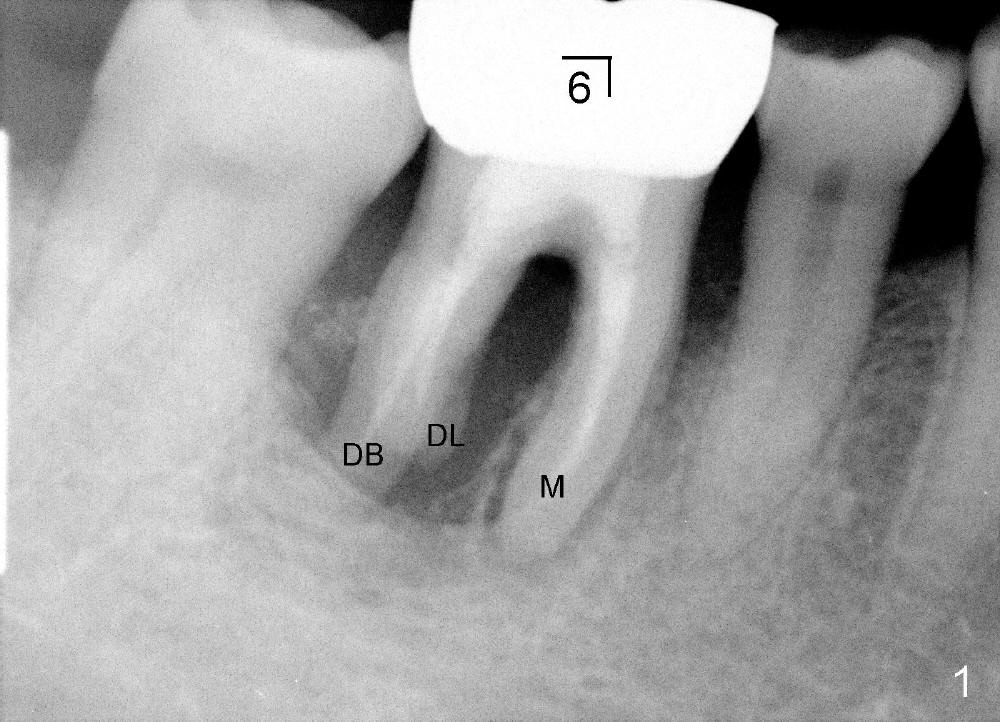

Fig.1,2 show bone resorption of the distobuccal and distolingual roots of the lower right 1st molar. The septum is present preop (Fig.2 >).